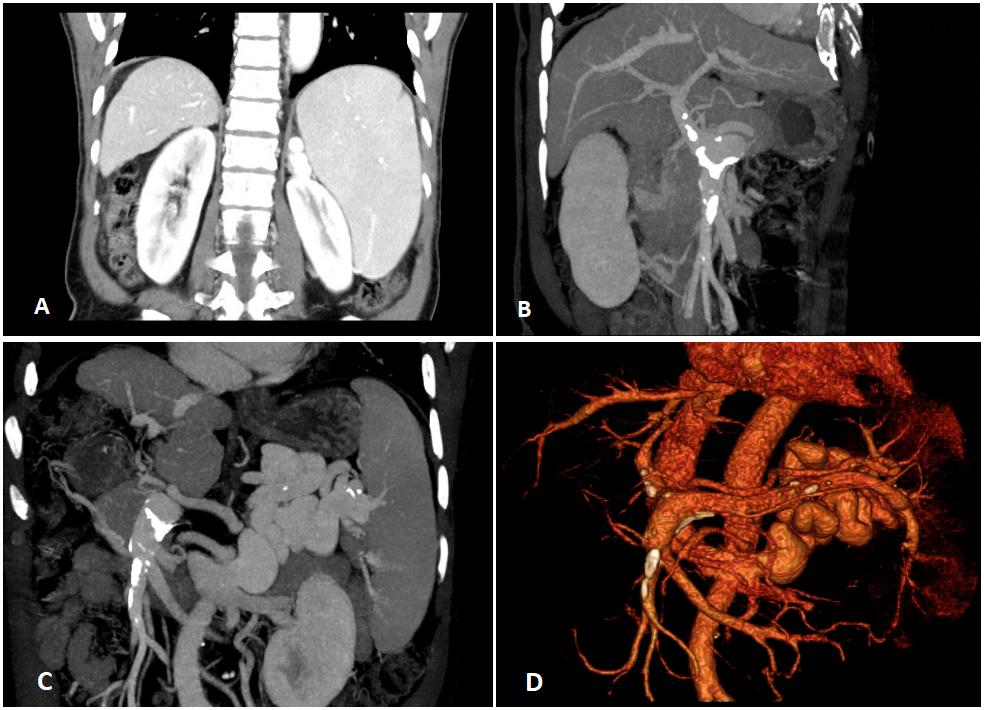

图2. 320门脉CT(2023-06-06)

肝右叶缩小,肝裂增宽,肝硬化、脾大、门脉高压伴侧枝循环形成。门静脉主干及脾静脉增粗,管壁散在钙化斑块,门静脉较宽径约1.5cm,脾静脉明显迂曲增宽,较宽径约1.4 cm,管壁光滑,官腔未见异常扩张及占位,未见充盈缺损;可见血管汇入左肾静脉,左肾静脉可见囊状突起影,大小约2.5 cm×2.2 cm×3.8 cm。

2023-06-03患者再次因“肝性脑病”入院,查血氨105.1 umol/L,入院后予以对症治疗后病情好转出院。出院后次日凌晨(2023-06-14)患者再次因“肝性脑病”发作且较强明显加重来我院。患者既往肝硬化病史30余年,影像学提示肝硬化、脾大征象,且血常规示三系减少,考虑患者存在门脉高压,而胃镜未见明显食管、胃底静脉曲张,且无明显腹水等门脉高压常见体征与症状。患者反复出现肝性脑病,肝酶轻微升高,血氨明显升高,而无明显消化道出血、便秘、利尿剂使用、放腹水等诱因,这与大部分肝硬化患者发生肝性脑病的表现不相符。随后的320门脉CT示门静脉主干及脾静脉增粗,脾静脉明显迂曲增宽,可见脾门区迂曲粗大血管汇入左肾静脉,左肾静脉呈囊状突起影。脾门处曲张静脉团汇入左肾静脉,脾脏血流经肾静脉回流至下腔静脉,降低了部分门静脉压力,故而食管、胃底静脉曲张不明显,但同时未经肝脏解毒的血液直接回流至下腔静脉以及肝脏灌注减少,导致了肝性脑病的发生。因此,综合考虑该患者为 C型肝性脑病(失代偿期肝硬化基础上合并粗大“脾-肾静脉分流”)。